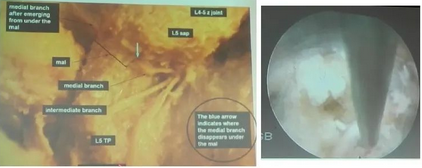

腰椎小关节综合征!